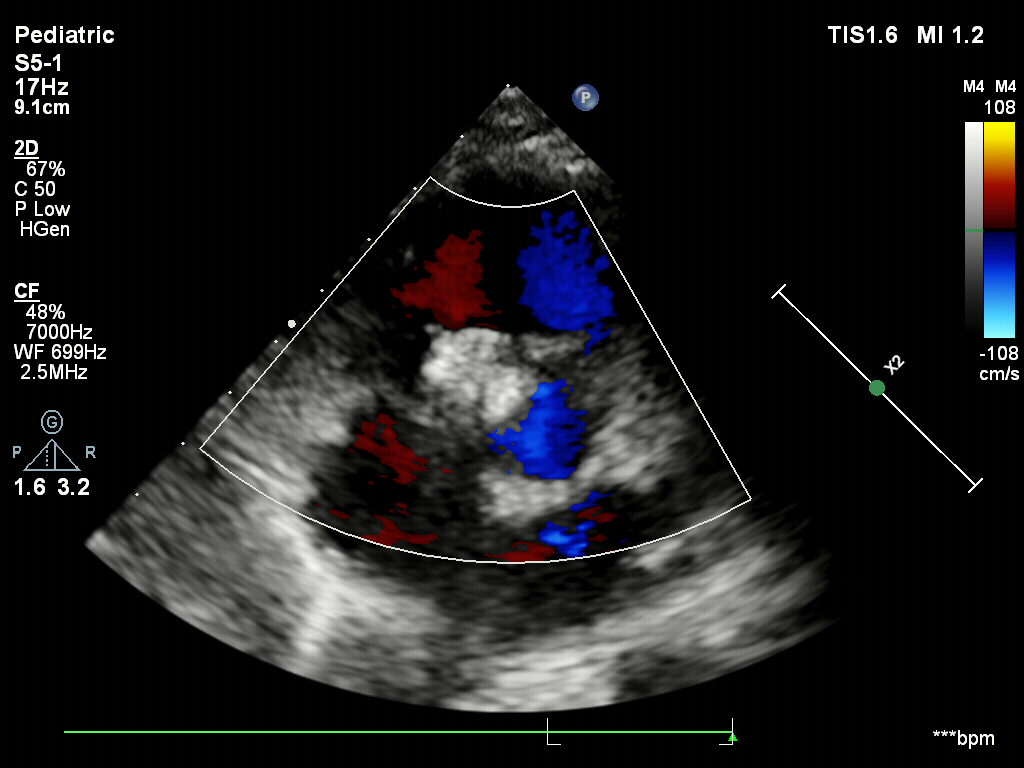

超声下确认封堵器位置正确

骑跨于室间隔两侧

封堵器的两个伞面与室间隔平行

释放封堵器后,超声下观察封堵器形态良好

无残余分流,封堵成功

封堵器稳定夹持在室间隔两侧,无残余分流